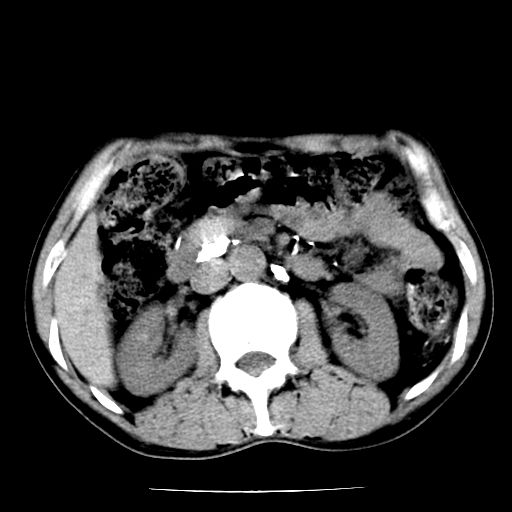

男,59岁,“结核性胸膜炎”30余年,胸部经常疼痛,多次x检查提示“肺部”炎症。腹部疼痛5日,b超提示:“肝内短管结石,余显示不清,建议进一步检查。”

两肺结核并右侧胸腔积液;脾脏、腹腔及腹膜后淋巴结结核[陈旧性];肝内胆管结石

胸部腹部都是结核(双肺。纵隔淋巴结,肝脏,脾脏,肠系膜)

一元论——结核。